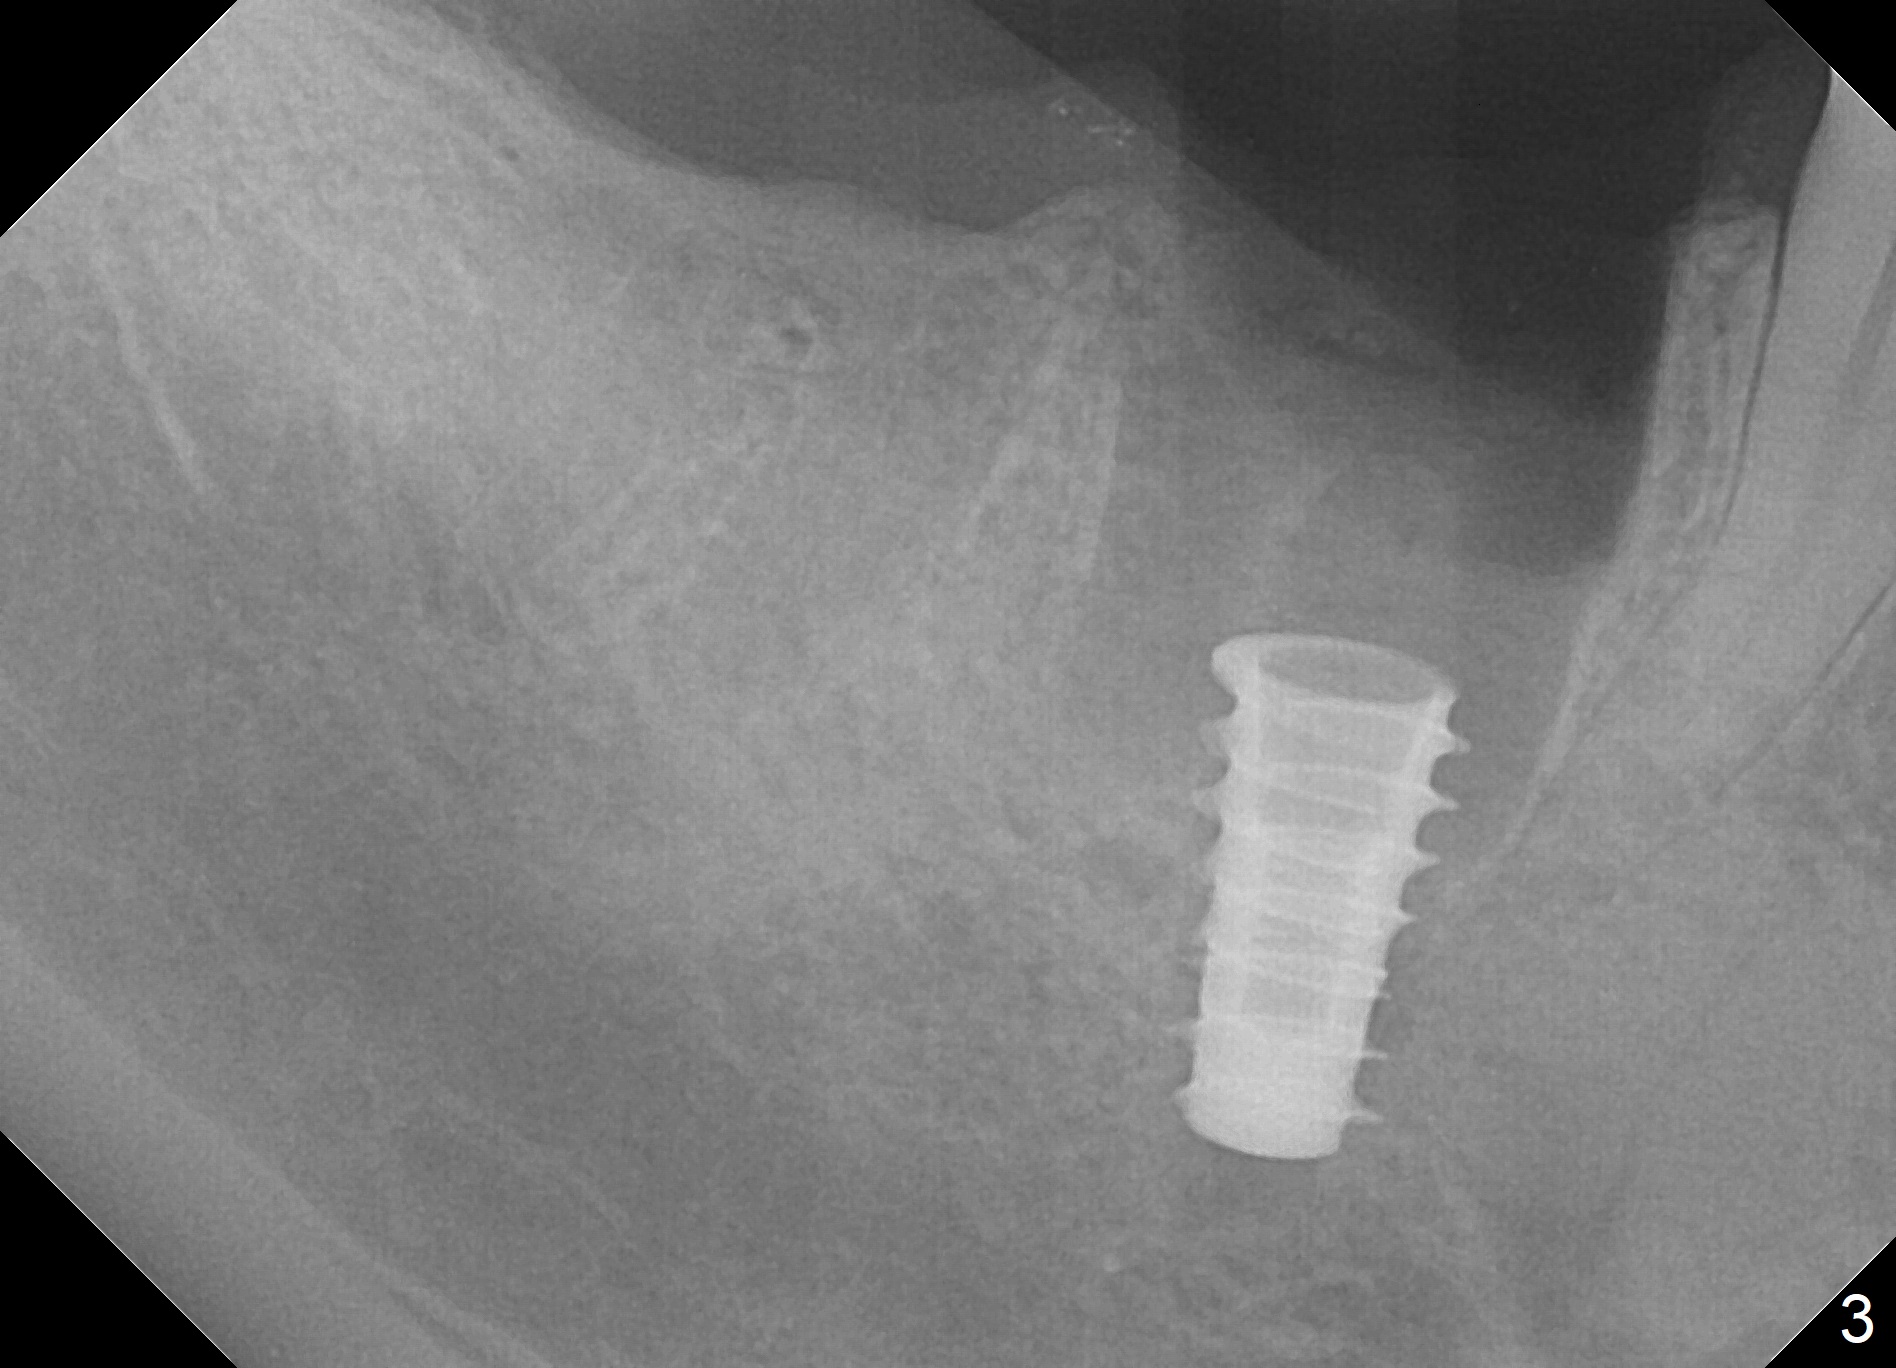

Extraction is difficult due to hard bone and brittle, curved roots of the tooth #30; initial depth in the septum is 14 mm (gingival level, Fig.1). Then the depth increases to 17 mm; with sequential osteotomy using 2.8 mm to 4.8 mm Magic Drills (MD), a 5x9 mm dummy implant is placed incompletely due to hard bone (Fig.2). After use of 5.3 mm MD for ~ 15 mm, the dummy implant is placed to the depth (Fig.3). The definitive IBS implant (5x13 mm) is placed with 50 Ncm; a 6.5x5.7(4) mm abutment is placed with allograft filling the gap (* and arrow).